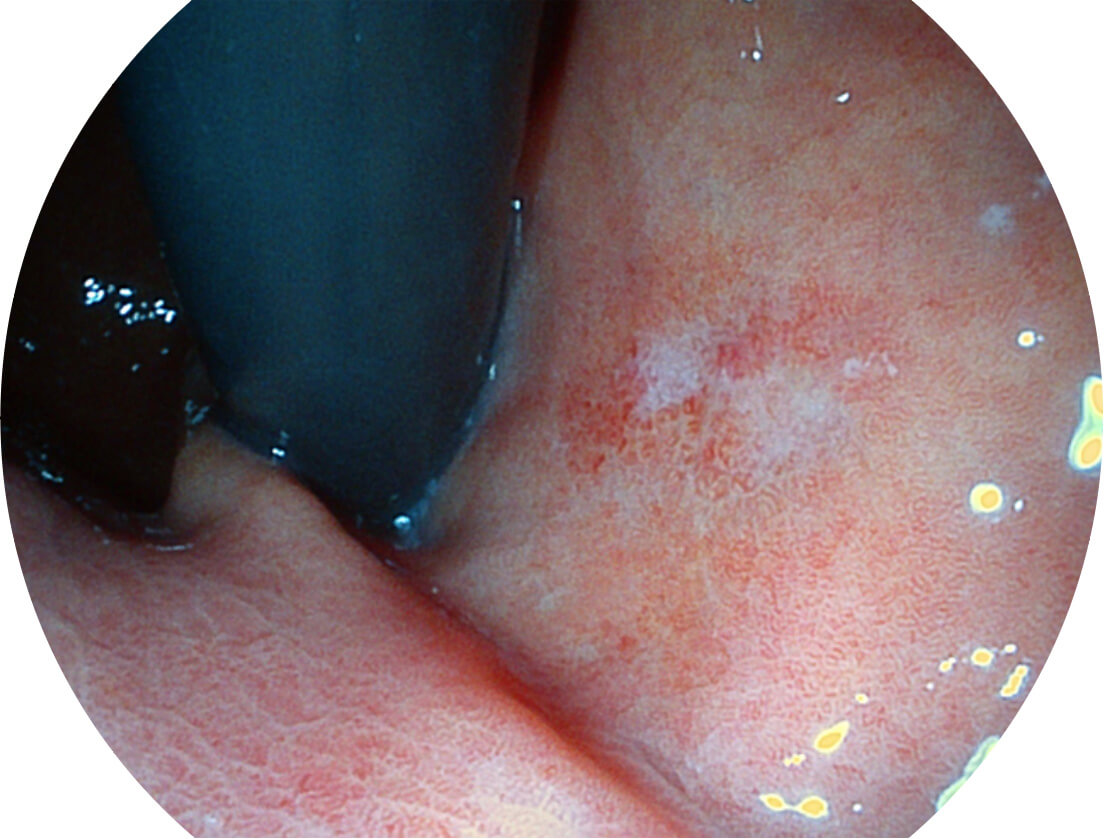

Spectral Focused lmaging, SFI

图像具有高亮度、高黏膜血管颜色对比度的特点,且不改变粘液、食物残渣、粪便的基本颜色,可在中远景下进行观察,助力消化道早期疾病的诊断。

白光图像

SFI图像